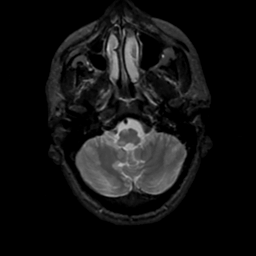

MR Study #7, March 24, 1991 -- Slice #8